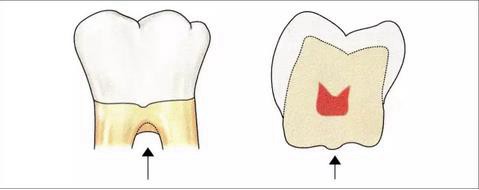

▼圖4 釉突的分類

也就是說在口腔外科,無論是切除療法還是再生療法,都會采取將釉突切除,將根面的牙骨質(zhì)露出,期待在術(shù)后的牙周組織可以擁有健全的附著狀態(tài)的方法。